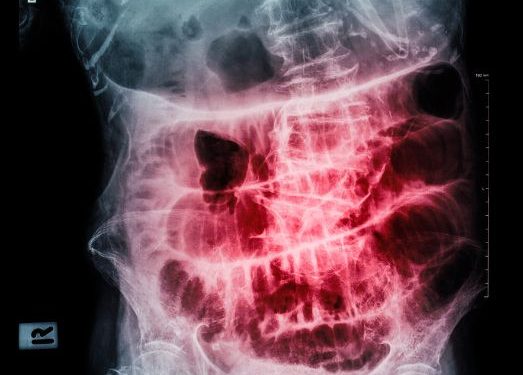

Your doctor will probably carry out some tests to help diagnose the problem. X-rays of your abdomen may be taken to determine the size of the bowel and whether there is an obstruction. This test can also help determine if there are any fluid levels that aren’t normal in your small bowel.